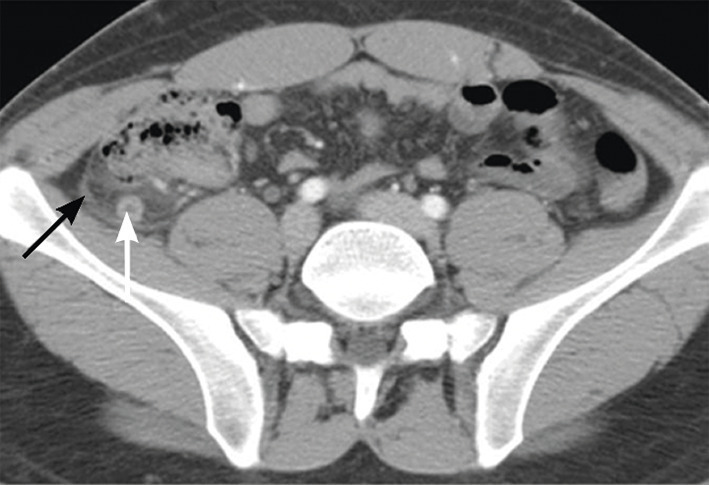

Un patient de 25 ans consulte pour des douleurs abdominales de la fosse iliaque droite. Pas de fièvre, CRP à 15. L’échographie abdominale est normale mais l’appendice n’est pas visible. Le scanner avec injection met en évidence, au temps portal, en arrière du cæcum, une structure tubulée borgne correspondant à l’appendice tuméfié, à paroi épaissie, intensément rehaussé (fig. 2 ; flèche blanche) avec infiltration de la graisse péri-appendiculaire (flèche noire). Le diagnostic d’appendicite aiguë rétro- cæcale est posé. L’échographie a été prise à défaut par la topographie atypique.